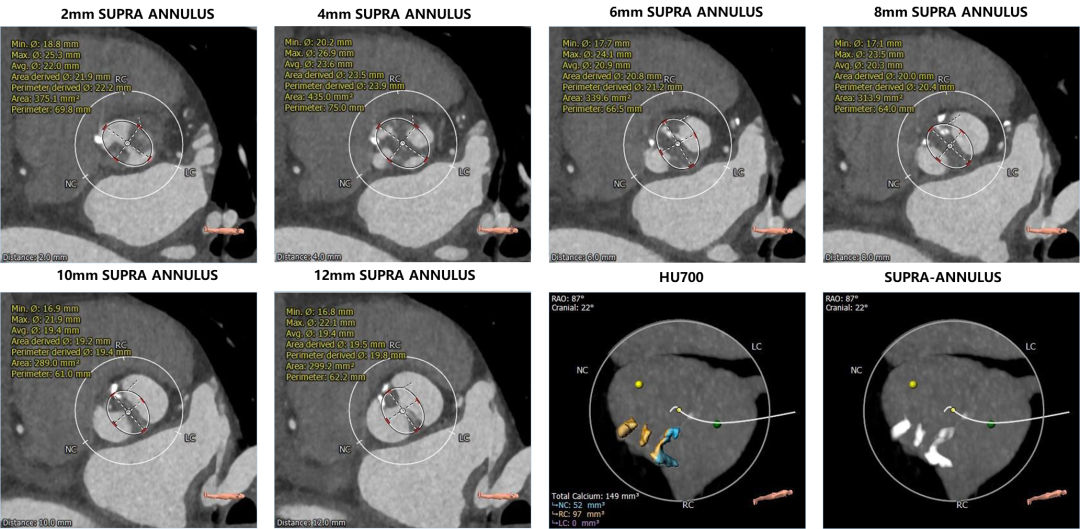

1. 主动脉瓣瓣环周长76.5,平均周长径24.6。

2. Type0型二叶式主动脉瓣,左右冠脉共窦,轻度钙化,钙化主要分布于瓣叶一侧对合缘周围,无冠窦底零星钙化,瓣叶明显增厚。

3. 左右冠开口高度可,切线位右冠窦瓣叶长度略长于瓣叶附着缘到冠脉下开口距离。

主动脉根部评估

瓣环上解剖结构评估